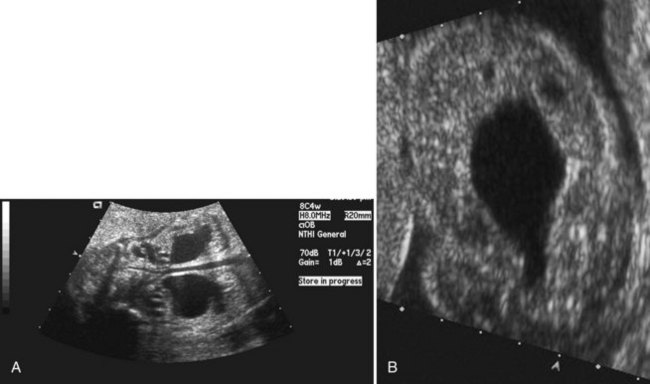

Young described type III valves as a membrane lying transversely across the urethra with a small perforation near its center (Fig. 126–3). The membrane is distal to the verumontanum and sometimes is elongated like a wind sock reaching the bulbous urethra (Field and Stephens, 1974). Type III valves make up only 5% of the total. Young described them as follows:

Figure 126–3 A, Voiding cystourethrogram demonstrates a typical type III posterior urethral valve with a transverse septum crossing the urethra at a right angle distal to the verumontanum. B, A cystoscopic image from the distal urethra shows the thin membrane and a small off-center opening.

The embryologic origin of type III valves has been attributed to incomplete dissolution of the urogenital portion of the cloacal membrane. Type III valves present in the same manner and are managed in the same way as the more common type I, although there is some evidence that type III valves have a worse prognosis (Rosenfeld et al, 1994).